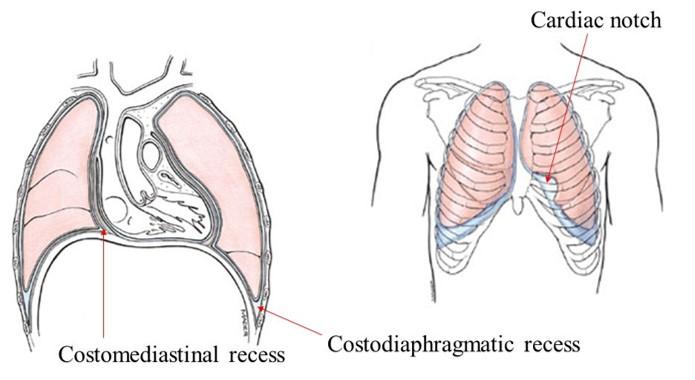

what is the:

costodiaphragmatic recess (CDR)...what is it a potential site for?

costomediastinal recess (CMR)

Potential pleural space located “between” the junction of diaphragm

and ribs

Potential site for pleural fluid accumulation

Potential pleural space located anteriorly “between” the junction of diaphragm and mediastimum

in picture you are looking from the top down...the CDR is wrapped around the 2 mickey mouse ears on the side where the ribs and diaphragm meet...the CMR is the small corners below the front circle on either side (slightly more yellow in color)

notice how the lung doesnt go all the way down and how there is a small corner where there can be an accumulation of fluid in the CDR

notice the cardiac notch in the CMR and how that can leave more space for the heart

the CDR is on the bottom of the lung in the kiddie-corner

the CMR is seen when you look down on the diaphragm from the top and see a small space in front